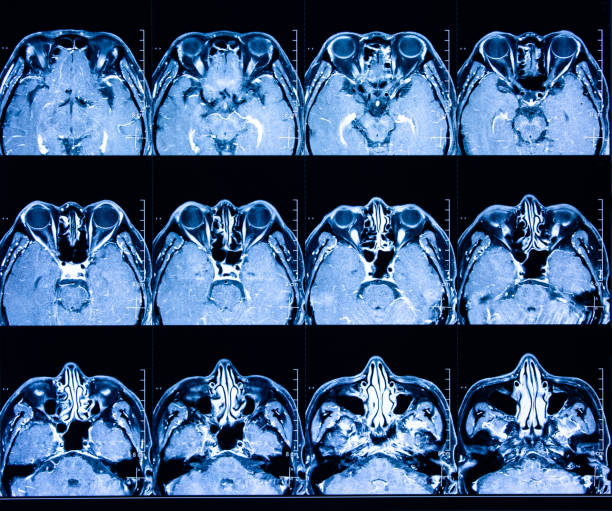

為了描述目的,患者按入組順序被賦予編號,并被連續分配到三組中的一組,每組三名。根據模型2分割,ICH體積范圍為0.1至54.9mL(平均ICH體積為23.5mL)。5名ICH患者受累于局限性腦葉,其余患者受累于基底神經節或外囊深處。3名患者的ICH位于丘腦(圖1),1名患者的血腫位于多個腦結構(即尾狀核、殼核和蒼白球)。平均而言,MSCs是在ICH后3天注射的。